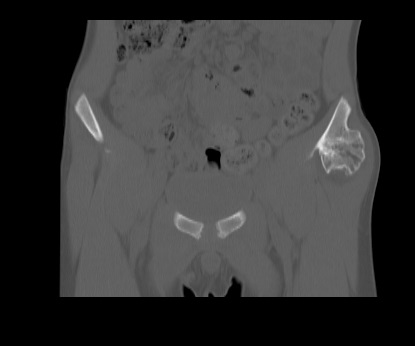

Es el tumor óseo primario benigno más frecuente con crecimiento en la superficie externa de un hueso.

Tiene cavidad medular que se continúa con la cavidad del hueso subyacente y un capuchón cartilaginoso recubriendo el espolón óseo, localizándose en metáfisis.

La localización más frecuente es en el fémur distal, y también alrededor de la rodilla o en la parte proximal del húmero.